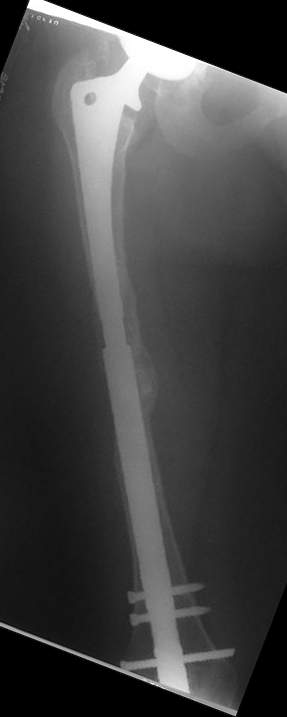

Спасибо за обсуждение. После нескольких дней тракции аппаратом сделали. Попытка закрытой репозиции не удалась из-за смещения по ширине, мешали фрагменты цемента. После их удаления репозиция получилась. Еще убрали немного цемента с ножки по латерльной стороне, чтобы обнажить 40-50 мм ее дистальной части, для плотной посадки гвоздя. Дальнейшее введение гвоздя было несложным. Протез показался нам стабильным в проксимальной части как латерально, так и медиально. Картинки в приложении.

THX for the discussion. After few days of traction by ex-fix the surgery was performed. An attempt of closed nailing was unsuccesful because of fragment translation, which was blocked by cement fragments. After removal of broken cement pieces reduction was reached "automagically". Also some cement from lateral part was removed by

chisel to expose distal 40-50 mm of the stem to allow tight fit of the nail. Further fixation by the nail was pretty easy and straightforward. Images attached. The stem looked stable in its proximal part both laterally and medially. Comments/critics are welcome.